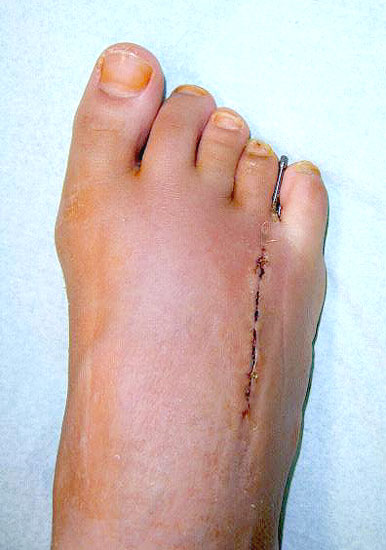

Das im Folgenden vorgestellte Operationsverfahren beschreibt die Kallusdistraktion von Metatarsalia nach den Prinzipien von Ilisarov 21 unter Verwendung eines internen, winkelstabilen Titan-Minifixateur (Klauser 2009). Der interne Distraktor ermöglicht während der Distraktions- und der Durchbauungsphase aufgrund seiner hohen Stabilität je nach Modell (18 mm, 23 mm) eine Verlängerung von bis zu 25 mm. Nach interner Anlage des Minifixateurs, meist lateral, kann über eine kontinuierliche Kallusdistraktion der Metatarsalebogen unter frühzeitiger Mobilisation im Gips oder Short-Walker rekonstruiert werden 15. Über einen interdigital und transcutan ausgeleiteten Aktivatorstab wird die Distraktion vom Patienten selber täglich morgens und abends durchgeführt. Zusätzlich vorliegende Strahlpathologien, wie zum Beispiel eine verkürzte Strecksehne oder ein kontraktes Metatarsophalangealgelenk können im Rahmen der Erstoperation ebenso therapiert werden wie z.B. ein Hallux valgus, ein Hallux valgus interphalangeus und/oder ein Digitus quintus varus (Klauser 2009). Nach Rekonstruktion des Metatarsalebogens wird in einem zweiten, kleinen Eingriff der Aktivatorstab über eine Spezialpinzette diskonnektiert und entfernt, wobei der Distraktor als interne Fixation belassen wird. Die Entfernung des Distraktors erfolgt in der Regel nach 9 – 12 Monaten, da es sich meist um angeborene kindliche Fehlbildungen handelt (Brachymetatarsie) und eine operative Intervention frühzeitig im Kindesalter erfolgen sollte (Klauser 2009).

• Erster Eingriff: Implantation des internen Distraktors, Osteotomie des verkürzten Metatarsaleknochens, ggf. Strecksehnenverlängerung, Grundgelenkrelease und dorsale Kapsulotomie.

• Zweiter Eingriff: Diskonnektieren des transcutan ausgeleiteten Aktivator, falls möglich, über eine kleine Inzision von 1,5 bis 2 cm, in der Regel jedoch über Eröffnen der alten Schnittführung mit ggf. Strecksehnenverlängerung und erneutem Grundgelenk-Release sowie ggf. Ausleiten einer Penroselasche oder einer Gentamycin-Palacos-Minikette.